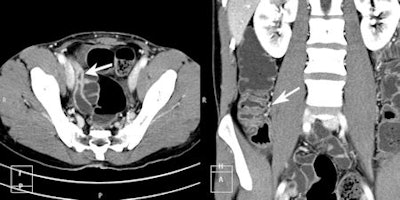

In the group of patients with known IBD, 3 (37.5% of subgroup) had signs of active inflammation and one patient had perianal fistulae. In the group referred with possible IBD, 3 (25% of subgroup) patients had signs of active IBD, one had ileocecal intussusception and one had a small-bowel mass lesion. This proved to be a hamartoma at histology following surgical resection.